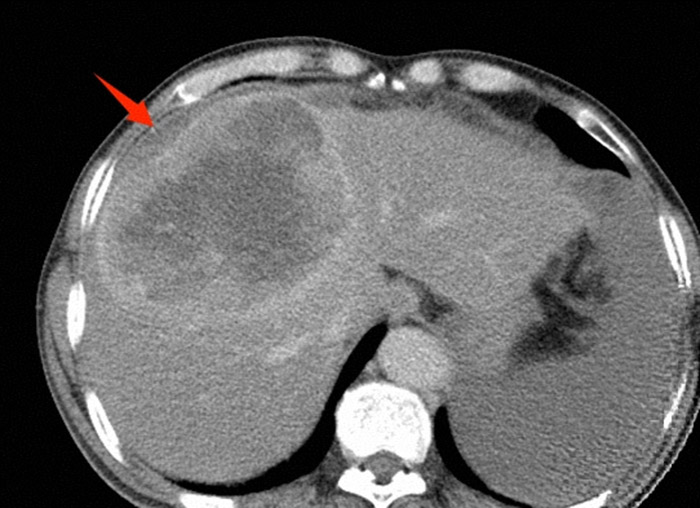

肝脏肿瘤破裂造成腹腔内出血

急诊检查结果让所有人都捏了把汗:血压最低跌至55/30mmHg,远低于正常标准;血红蛋白仅85g/L;腹部CT清晰显示肝癌病灶破裂,伴有大量出血。诊断性腹腔穿刺抽出不凝血——这是肝癌患者最凶险的并发症之一,若不能在短时间内止血,失血性休克随时会夺走生命。